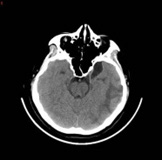

A 32-year-old woman in her 10th week of pregnancy presented to our hospital with nausea, vomiting and headache 10 days ago, increased nausea and vomiting with blurred vision and poor response 7 days ago, and yesterday developed a fever with a temperature of up to 38°C. She was admitted with a diagnosis of Wernicke’s encephalopathy combined with severe pregnancyrelated emesis. The patient had stopped menstruating 10 weeks earlier, denied oral contraceptive use, denied a family history of hereditary propensity to thrombosis, and denied a history of haematological disorders, autoimmune diseases, and intracranial and extracranial tumours. On admission, the patient’s main symptoms were persistent headache, nausea and vomiting, with normal vital signs and muscle strength. Her D-dimer level was 5.98 mg/L and β-human chorionic gonadotropin >10,000 IU/L. Other laboratory tests were essentially normal, such as routine blood, coagulation, urine, liver function, renal function and protein C. At the time of admission, the cranial CTV+CTA showed a tortuous left anterior cerebral artery segment A1, left jugular vein, left transverse sinus and sigmoid sinus thrombosis (Figure 1A), and cranial CT showed a large lamellar high-density shadow in the left temporal lobe surrounded by a lamellar low-density shadow. The diagnosis was venous sinus thrombosis combined with left temporal lobe cerebral haemorrhage (Figure 1B). He was admitted to the Intensive Care Unit(ICU) on a conservative basis, and a neurological consultation revealed poor mental health and limb weakness (4/5), with no other focal neurological deficits identified. After 3 days of conservative treatment, symptoms of drowsiness, blurred vision and impaired consciousness developed and CT showed an increase in the area of blood accumulation in the right ventricle (Figure 1C). An emergency mechanical thrombectomy was performed, after which the occluded left transverse and sigmoid sinuses were successfully recanalized and the haemorrhagic focus did not continue to increase in size (Figure 1D). Due to the presence of some residual thrombus, she continued postoperative LMWH therapy and urokinase thrombolysis, after which she was discharged in a stable condition with significant improvement in her symptoms. At the 1-month follow-up after discharge (Figure 1E), no recurrence of the disease was noted.